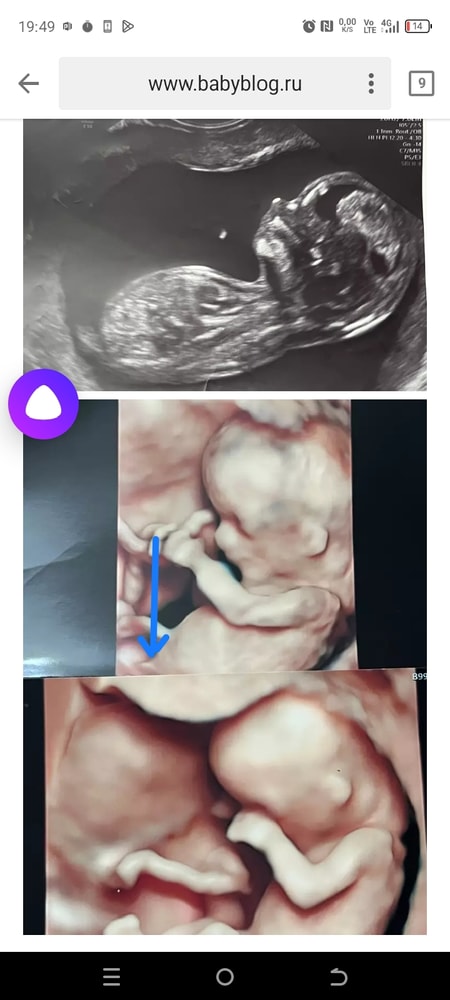

На 3 фото выглядит так, будто двойня🤣обман зрения такой, не сразу поняла)

Яна, хз 😂 я не теряю надежду. Но у них пока половой бугорок, органы ещё не сформированы